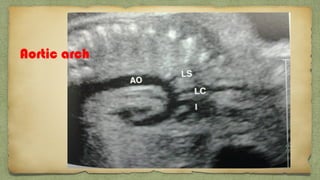

Aortic arch

Ductus

arch